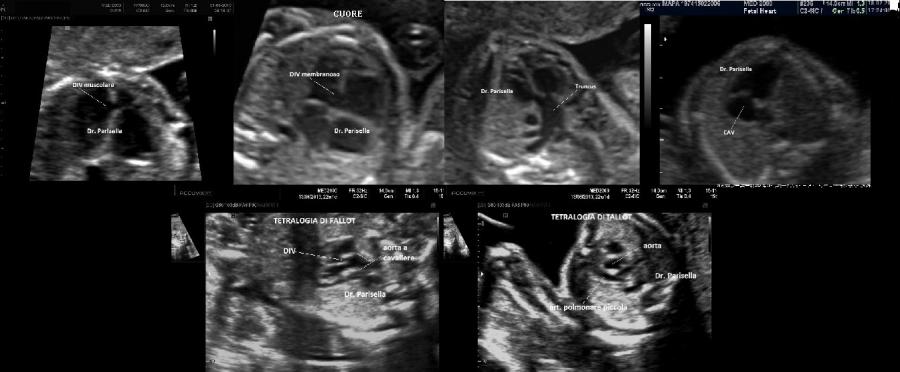

Le lesioni caratteristiche a carico del SNC sono rappresentate  da idrocefalo grave, con ventricoli aperti nello spazio subaracnoideo, ipoplasia cerebrale, anomalie della linea mediana e del setto pellucido (agenesia del corpo calloso); possono essere presenti encefalocele occipitale, una caratteristica conformazione del forame magno “key-hole shaped”, mandibola piccola e naso malformato, labio-palatoschisi. Caratteristica è la polidattilia postassiale alle mani e preassiale ai piedi (l'alluce duplice è altamente caratteristico, quasi esclusivo, di questa condizione morbosa). Segnalati anche piede torto e difetti cardiovascolari (difetti del setto atriale; atrio unico). Come ha segnalato lo studio di Salonen e coll. (1981) condotto su 28 neonati di 18 famiglie, l'esito abituale della gravidanza è la nascita di feto morto o morte in epoca neonatale.